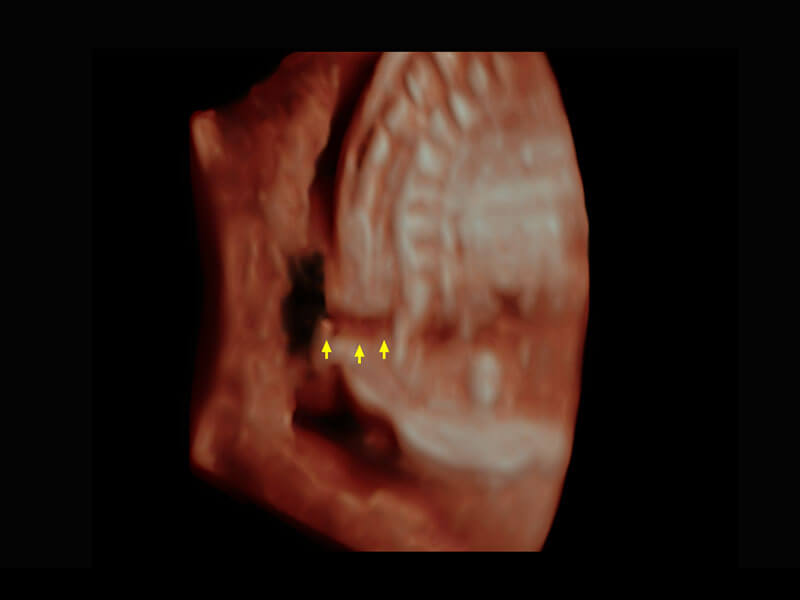

早孕-胎心

高分辨率容积成像-早孕胎儿

光影成像-孕囊